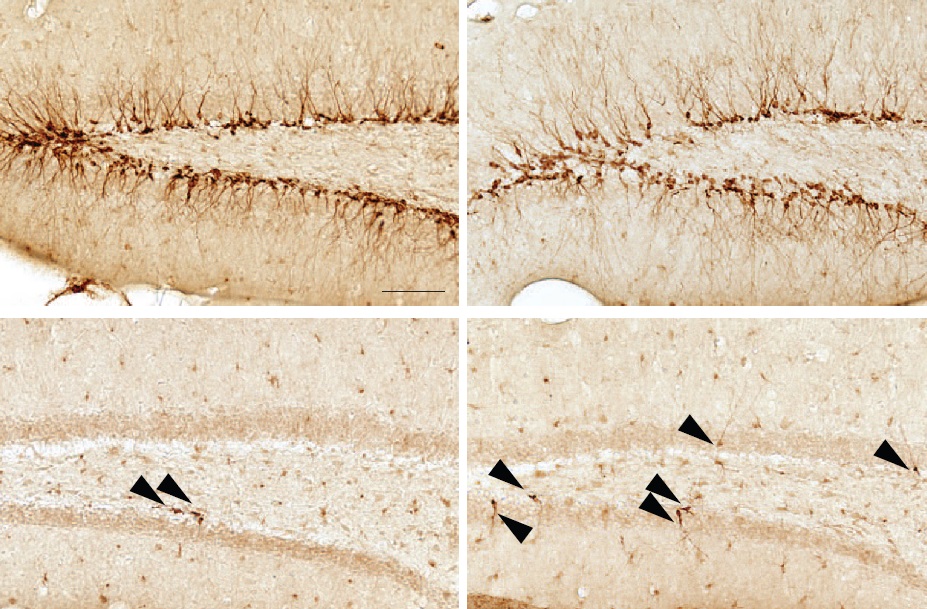

Crédito da imagem – Figura mostrando os neurônios dos camundongos que receberam as transfusões. Cada ponto marrom é um neurônio. Note o maior número de neurônios no idoso (abaixo à direita) que recebeu a transfusão de sangue de animais jovens. Note também o menor número de ramificações nos neurônios do jovem que recebeu transfusão de sangue de um idoso (acima à esquerda).

Drácula estava certo! Cientistas encontraram uma maneira de reverter o envelhecimento dos neurônios. Camundongos jovens receberam uma transfusão de sangue de camundongos idosos e camundongos idosos receberam sangue de jovens. Um grupo de pesquisadores da Universidade de Stanford na Califórnia queria saber qual o efeito dessas transfusões sobre o cérebro e publicou os resultados na Revista Nature. Com o envelhecimento, neurônios perdem suas conexões e começam a morrer até que, finalmente, o cérebro encolhe e torna-se menos eficaz. Uma região chamada hipocampo, crucial para a memória e aprendizagem, é um dos primeiras áreas do cérebro a se deteriorar com a idade, causando falhas na memória e no raciocínios. Mas, os camundongos velhos que receberam sangue jovem experimentaram uma explosão de crescimento de neurônios no hipocampo. Eles tinham de três a quatro vezes mais neurônios do que os camundongos idosos que não receberam transfusão como muitos camundongos recém-nascidos. Mas isso não foi tudo: o sangue de idosos teve o efeito oposto sobre o cérebro de camundongos jovens, bloqueando o nascimento de novos neurônios e deixando-os parecendo velhos antes do tempo. Como é o cérebro que controla nosso organismo inteiro se isso também acontecer em outras áreas do cérebro pode ser que haja um rejuvenescimento das funções de todos os nossos órgãos. Esta descoberta é uma esperança para o tratamento de doenças neurodegenerativas relacionadas a idade em que há morte neuronal como Parkinson e Alzheimer. O que atualmente está sendo testado em humanos. Então, Drácula estava certo, o sangue de jovens pode ser a fonte eterna da juventude.